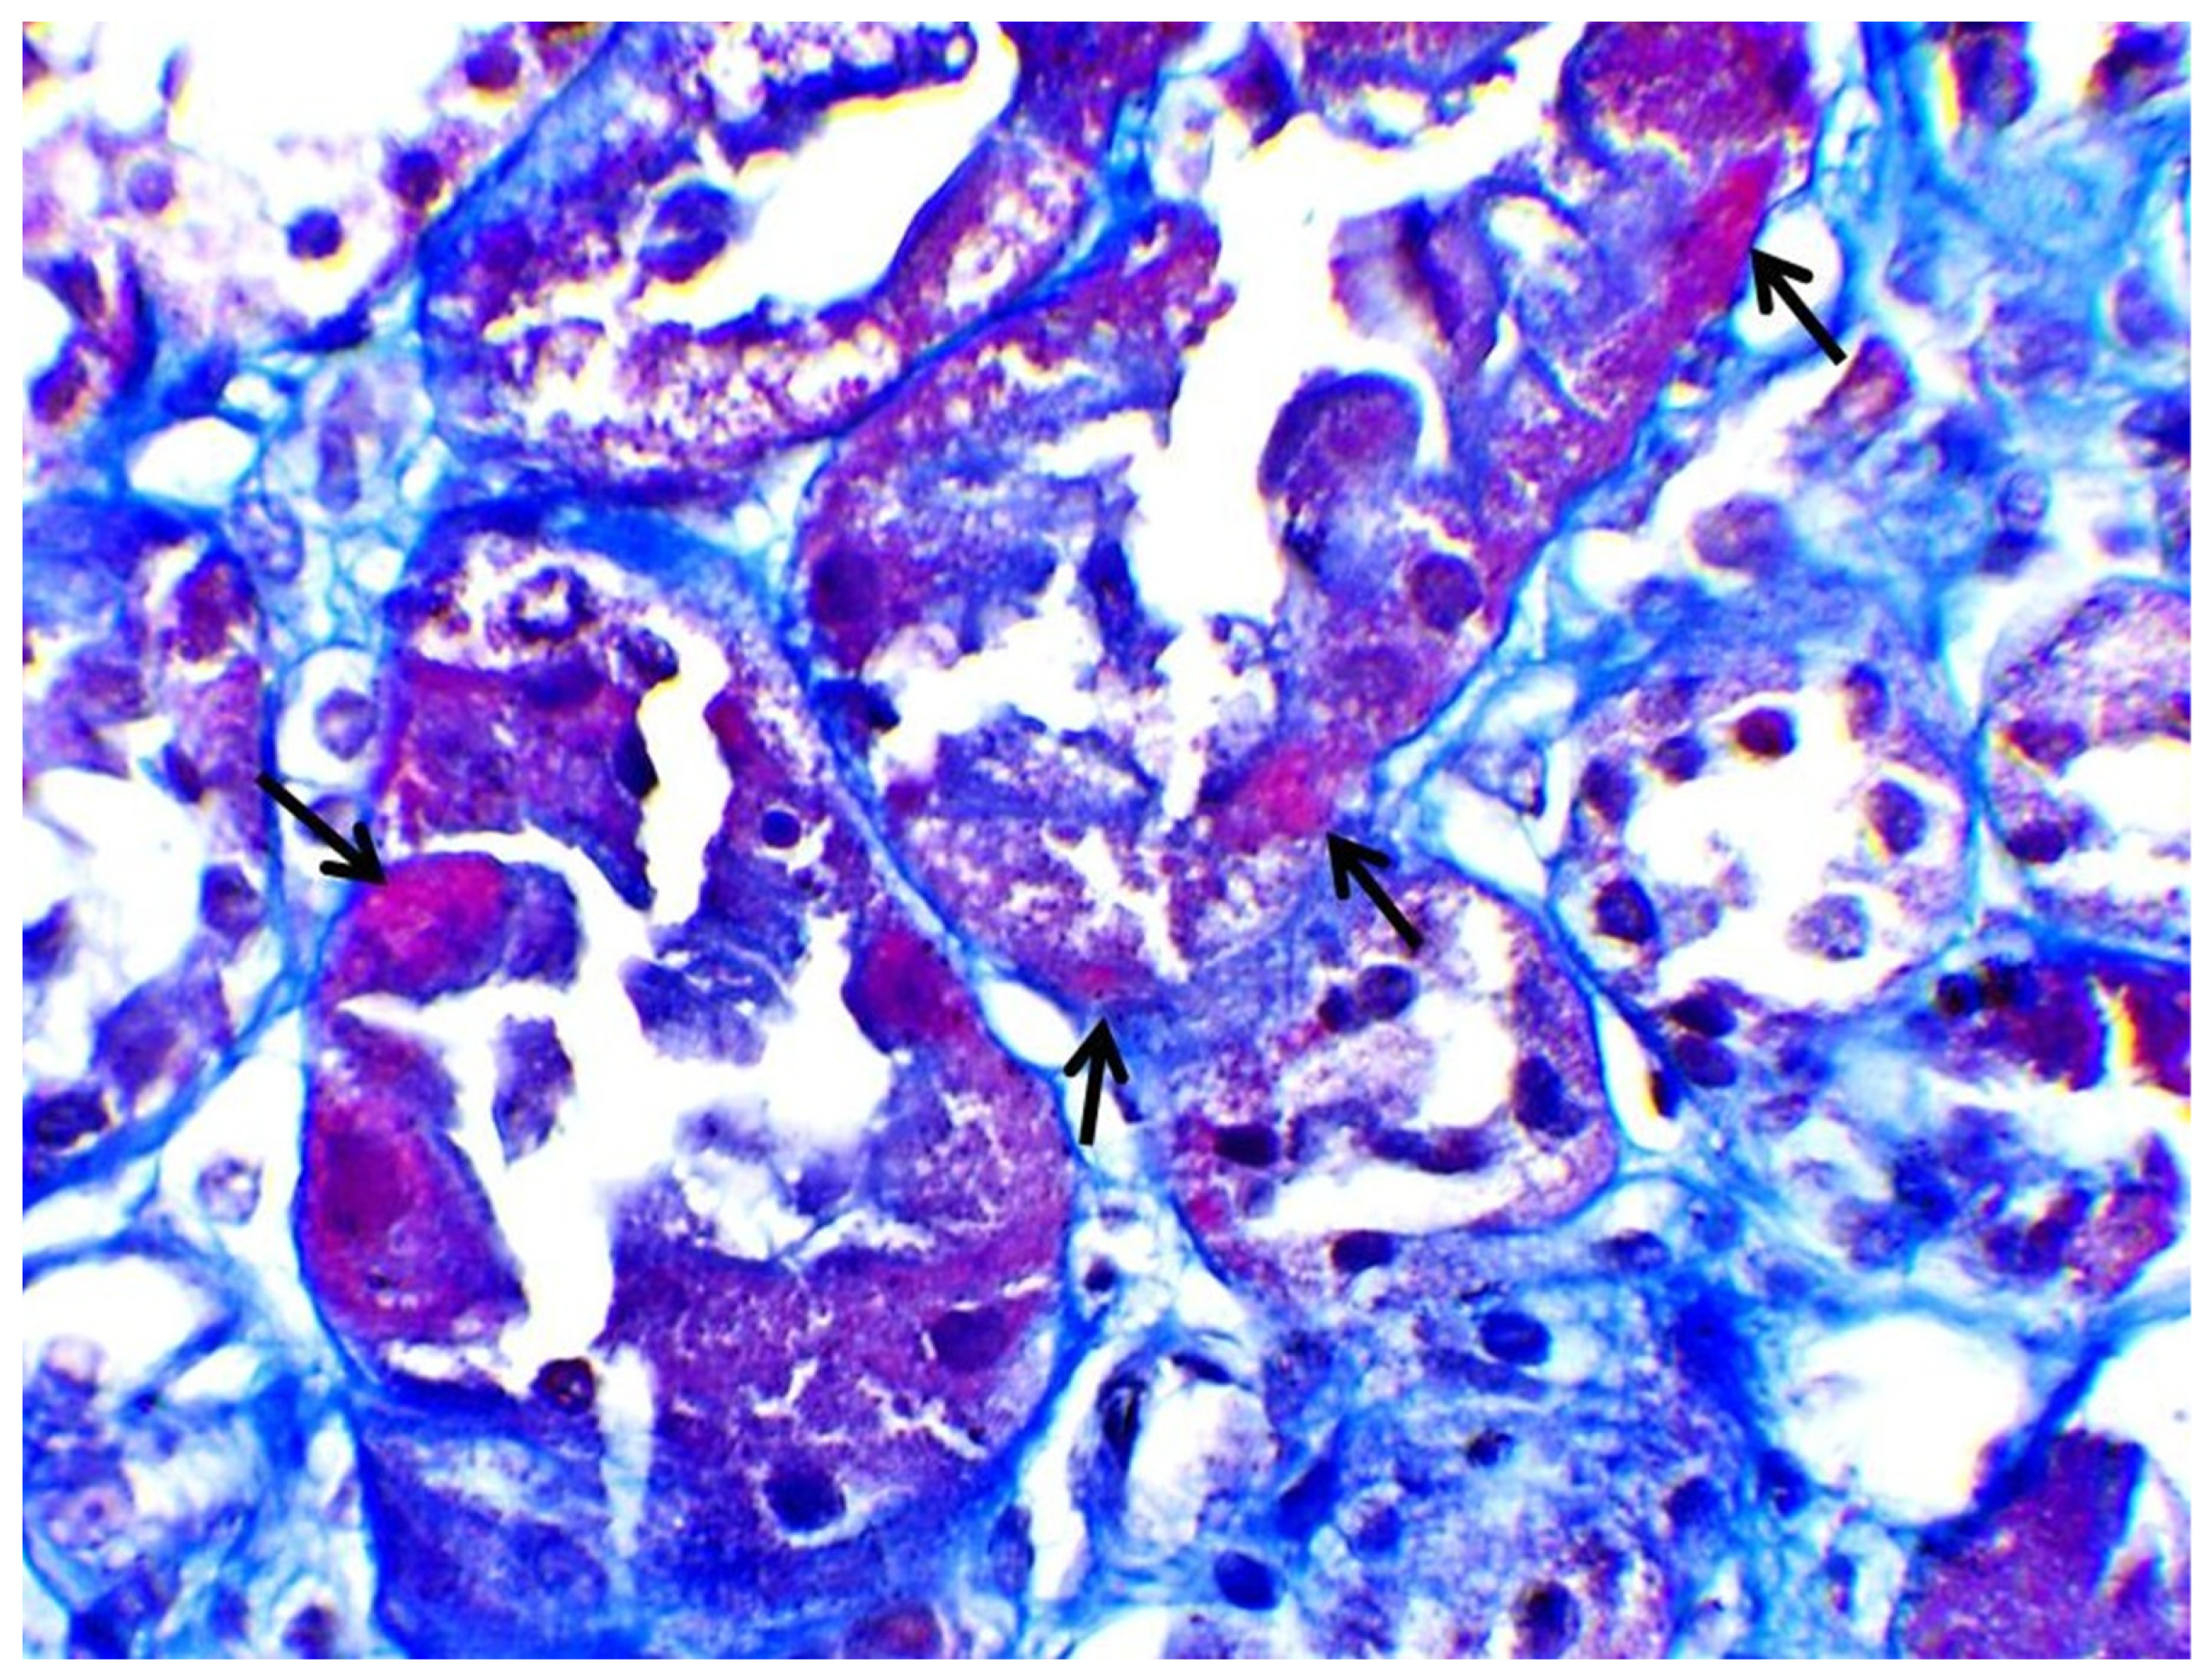

| Biopsy | Proximal Tubular Injury | Not performed | Not performed | Not performed | Proximal Tubular Injury |